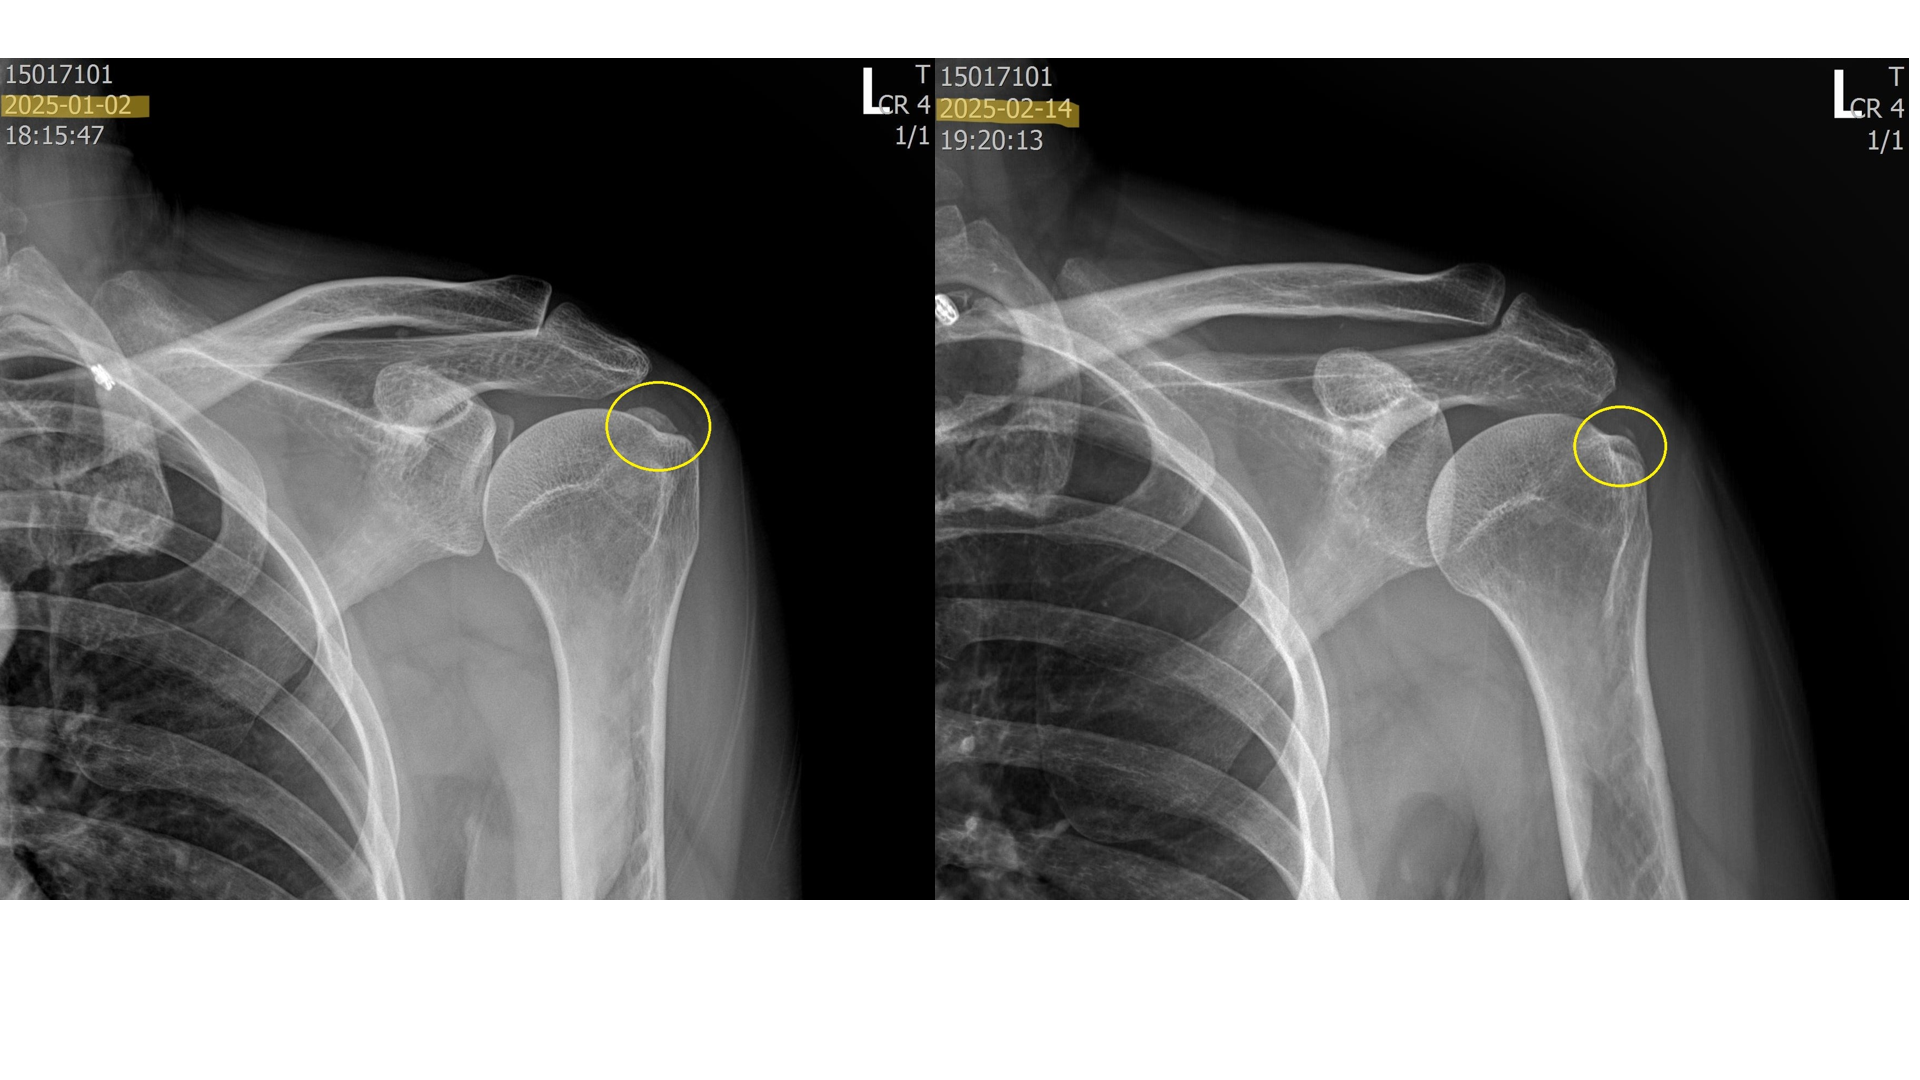

석회 흡입술 + 체외충격파 시술을 통해 석회가 얼마나 제거될까요?

위의 사진은 실제로 내원하여 치료받은 환자들의 x-ray 입니다. 이 환자분들은 약 5회에 걸쳐 섭회흡입술 + 체외충격파시술을 받은 분들입니다. 보시다시피 드라마틱하게 석회가 제거된걸 볼 수 있습니다.

혹시 석회성 건염으로 고생하시거나 진단받은 분이 있다면 섭회흡입술 + 체외충격파 시술을 함께 고려해보시길 바랍니다.